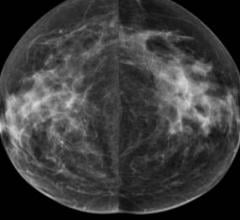

Mammography is a breast imaging technique that uses X-rays to diagnose and locate tumors of the breasts.

Despite decades of progress in breast imaging, one challenge continues to test even the most skilled radiologists ...

Two decades of research on the masking risk of dense breast tissue by mammography screening is indisputable. As the ...

Hologic, Inc. announced that the Genius 3D Mammography exam is now the only mammogram that is FDA-approved as superior ...